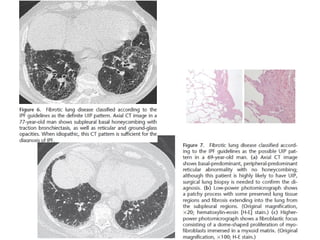

Fibrosis pulmonar idiopática •Causa desconocida • Es la más común de IIP 50-60% • Patrón histológico y TC: UIP exposición a drogas y polvo, neumonitis hipersensibilidad crónicas, colágeno y asbestosis D: excluir causas

• 11.

UIP histología • Combinaciónheterogénea de inflamación intersticial, fibrosis y panalización con áreas normales • *biopsia puede desestimarse

UIP TC • Fibrosiscon áreas normales. • Disminución de volumen pulmonar • Opacidades reticulares • Vidrio esmerilado • Predominio en regiones basales y subpleurales • Distorsión arquitectónica con bronquiectasias por tracción secundaria a fibrosis. • Panal de abejas (2-20mm) • Linfoadenopatías mediastínicas pequeñas.

DD UIP CT •AR, Esclerodermia (esófago dilatado) • Asbestosis ( derrame pleural, bandas parenquimatosas) • Neumonitis por hipersensibilidad crónica: fijarse en signos de atrapamiento aéreo, Respeto de bases o cuando hay nódulos centrolobulillares. • Sarcoidosis terminal: fibrosis en segmentos posteriores de lóbulos superiores o perihiliar, o nódulos perilinfáticos. • NSIP • Complicaciones: • Exacerbación, DAD • Cáncer pulmonar 10-15% bases